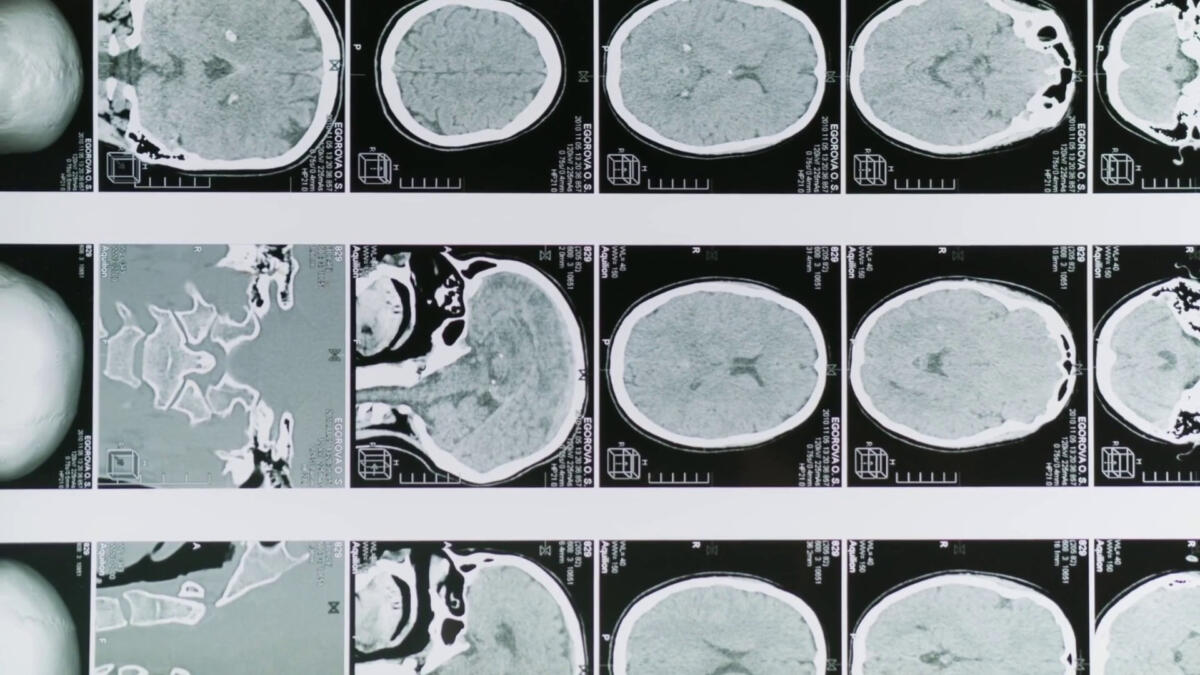

ROMA (ITALPRESS) – Una sperimentazione condotta per la prima volta su un campione di pazienti umani ha rivelato che la combinazione di curcumina e polidatina – due molecole naturali – migliora l’efficacia della terapia chemioterapica nel trattamento del glioblastoma, un tumore cerebrale particolarmente aggressivo. Il test è stato condotto da ricercatori dell’Istituto di farmacologia traslazionale del Consiglio nazionale delle ricerche e della Fondazione per la ricerca di terapie oncologiche integrate, e con la consulenza epidemiologica del Policlinico Gemelli.